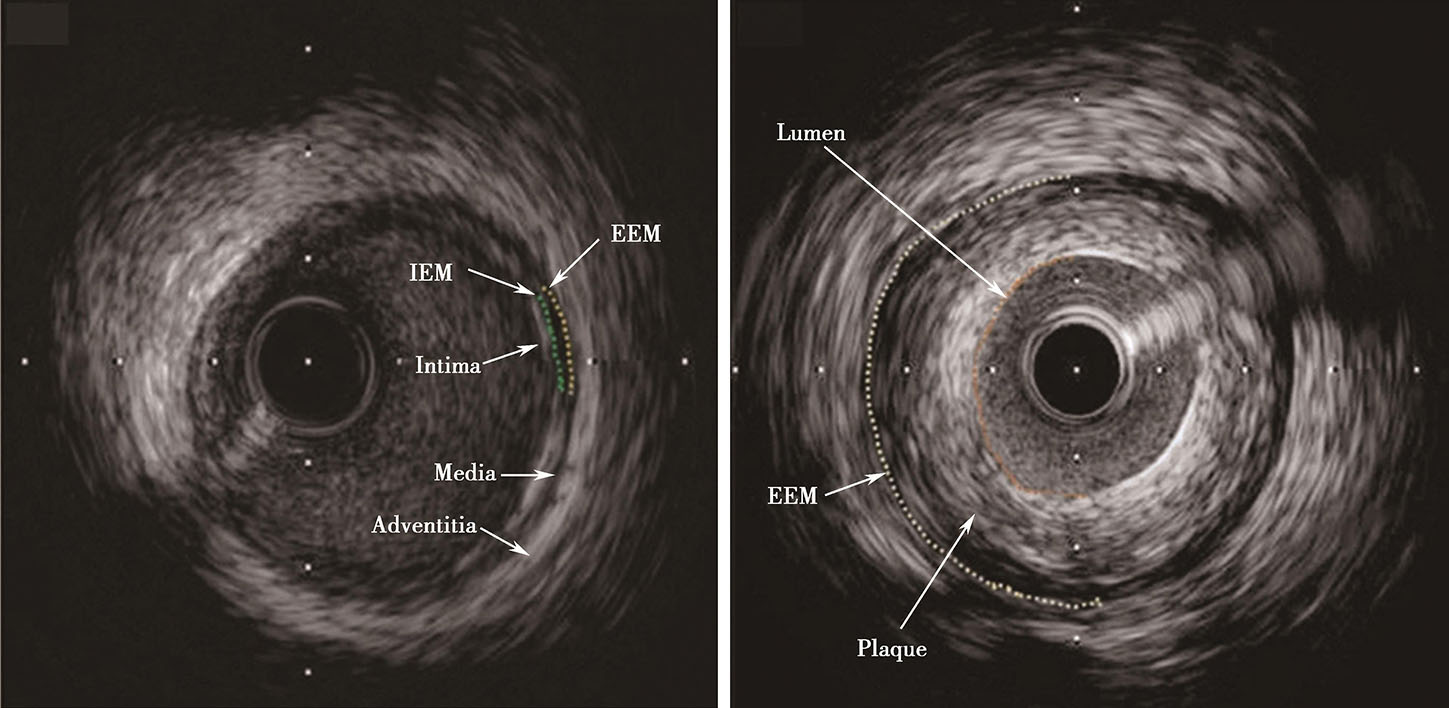

血管内超声图像解读

图片尺寸1694x1792